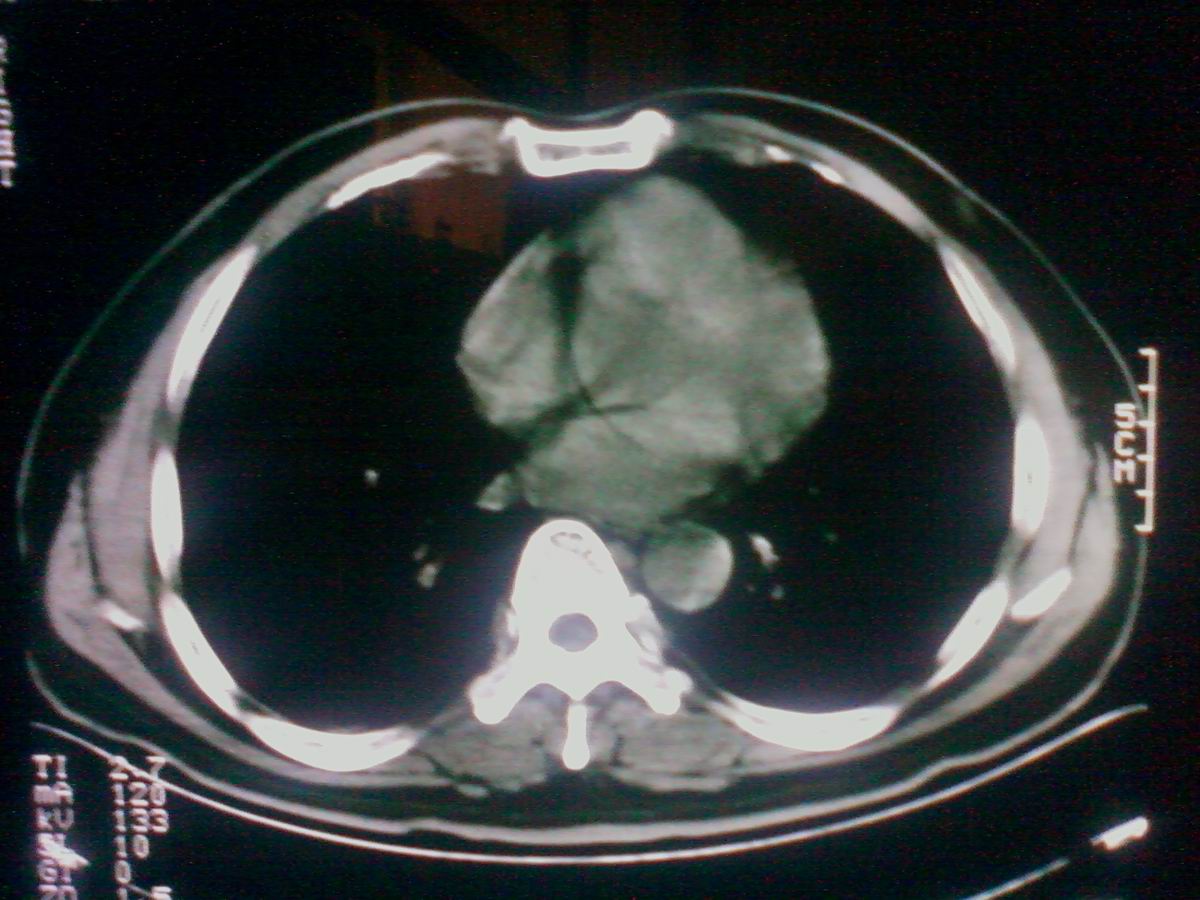

气管后部见半圆形软组织密度病灶,考虑占位,建议气管镜除外鳞癌。

气管上段的肿瘤多为良性乳头状瘤,气管下段的肿瘤多为鳞癌,气管中段的良恶性各占一半。本例位于气管下段,先按恶性处理。不过纤支镜是免不了的。

气管有占位鳞癌、腺样囊性癌、类癌、粘液表皮样癌。

进修时见过一例类似的并例,不过肿块位置较高,在胸锁关节以上的气管内,如果不是扫描得高,几乎忽略掉。后来支气管镜检为鳞癌。

考虑气管癌可能性大。